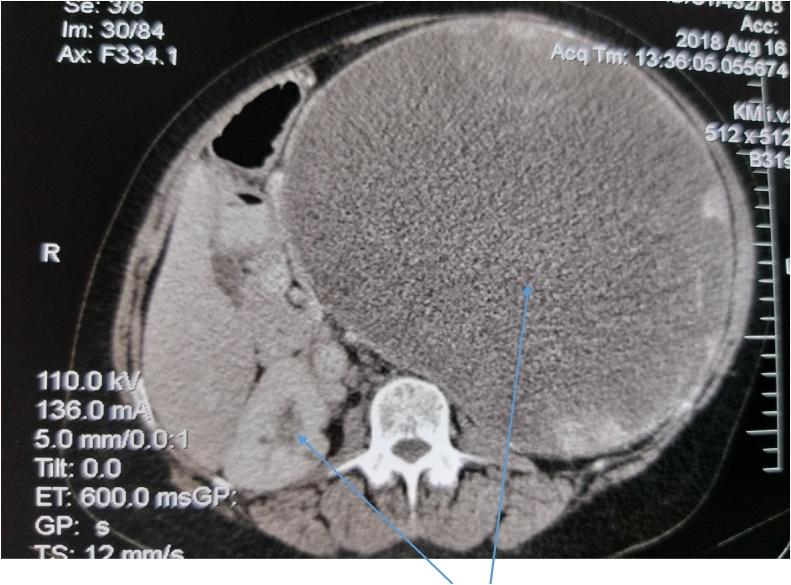

Two female patients aged 22 years and 65 years respectively, and an 11-year-old boy presented with giant pancreatic pseudocysts (>10 cm in diameter each) to our unit and were successfully managed. They all underwent exploratory laparotomy and cysto-gastrostomy with good outcome.

两名分别为22岁和65岁的女性患者以及一名11岁男孩因胰腺巨大假性囊肿(直径均>10 cm)前来我院就诊,并成功接受治疗。他们均接受了剖腹探查术和囊肿胃吻合术,效果良好。